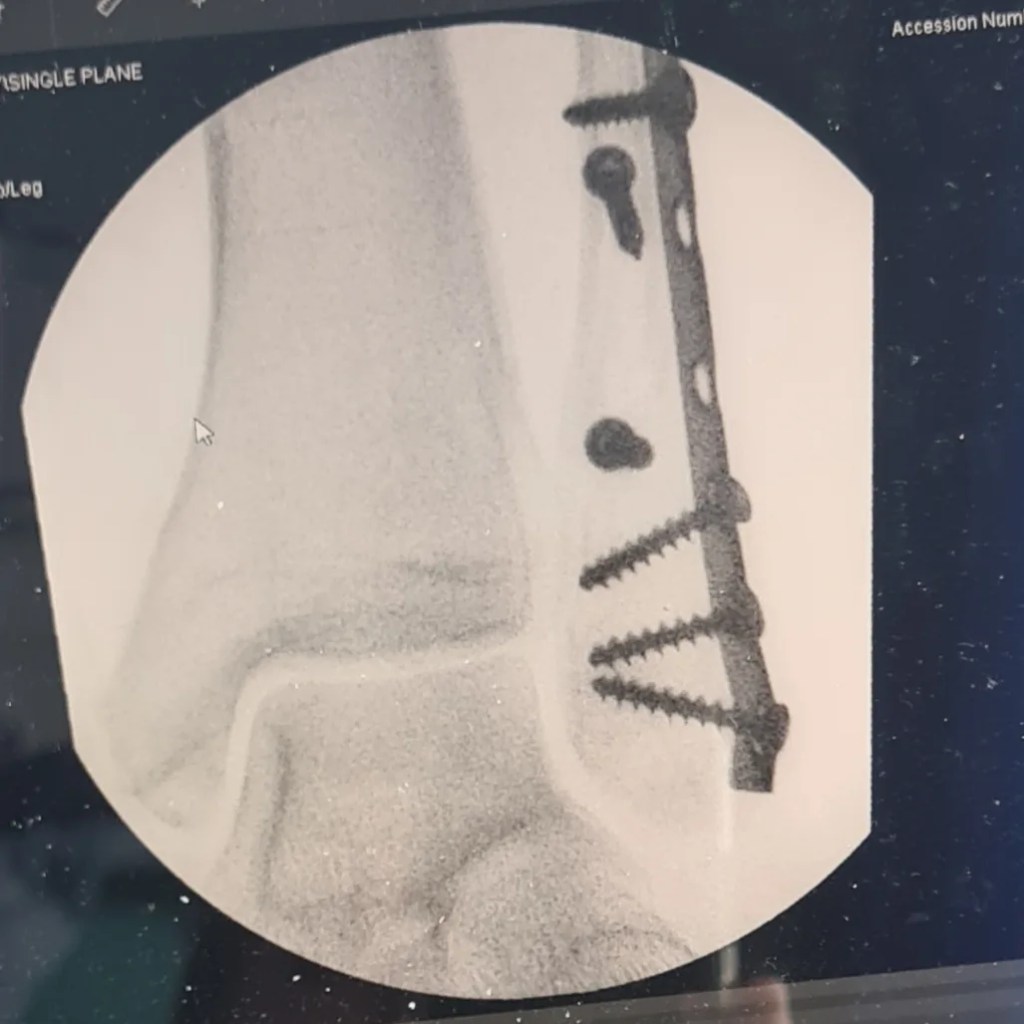

But I will never be the same again

Metalwork and scarring

Will mark the spot forever

I just tripped

Just a tiny trip

Just a slip

Just